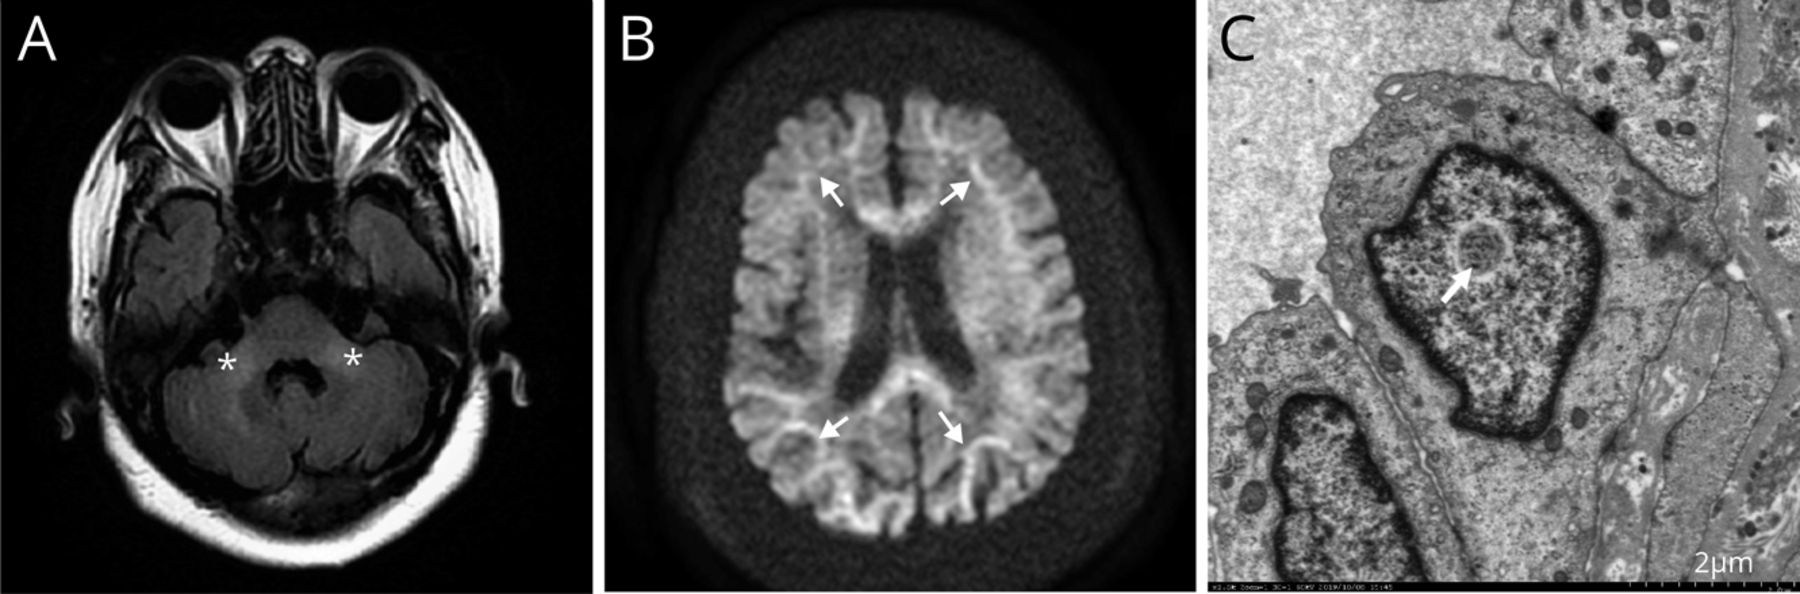

最初的检查包括血细胞计数;肝、肾、甲状腺功能评估;测定电解质、葡萄糖、氨和血清铜蓝蛋白;CSF分析;肌电图;头颅核磁共振。除t2加权液体衰减反转恢复(FLAIR) MRI序列显示双侧小脑中梗(MCPs)和脑室周围白质(图,一个)。

脑MRI显示双侧小脑中梗液体衰减反转恢复序列(A,星号)及皮质髓质交界处和胼胝体扩散加权序列(B,箭头)高。(C)皮肤活检显示汗腺细胞核内包体(箭头)。

为了更好地描述这些异常,我们进行了磁共振血管造影(MRA)、扩散加权成像(DWI)、表观扩散系数(ADC)作图和对比增强t1加权成像(T1WI)。脑MRA和增强T1WI结果无显著性差异。DWI显示双侧MCPs高强度,ADC映射显示等强度。此外,DWI和ADC映射显示皮质髓质交界处和胼胝体(图B)。

NIID的临床异质性增加了生前诊断的难度。在某些亚洲人群中(如日本人和中国人),NIID比FXTAS更常见。神经影像学和皮肤活检有助于其生前诊断。NIID的神经放射学特征包括DWI上皮质髓质交界处高信号,FLAIR序列上肾旁区高信号及双侧MCP征象。5DWI上沿皮质-髓质交界处的高强度信号与星形胶质细胞中的病理性海绵状改变和嗜酸性透明质包体相关,这损害了白质。6然而,其他疾病(包括FXTAS)也报道了NIID的主要放射学征象,尽管DWI的皮层下脑高信号对NIID的特异性高于FXTAS。1皮肤活检是区分NIID与其他疾病的必要手段。7由于FXTAS与NIID的临床表现、影像学特征、组织病理学表现,甚至分子基础(即扩大的CGG重复序列)可以重叠,基因检测可以进行FMR1区分这两种情况很重要。1